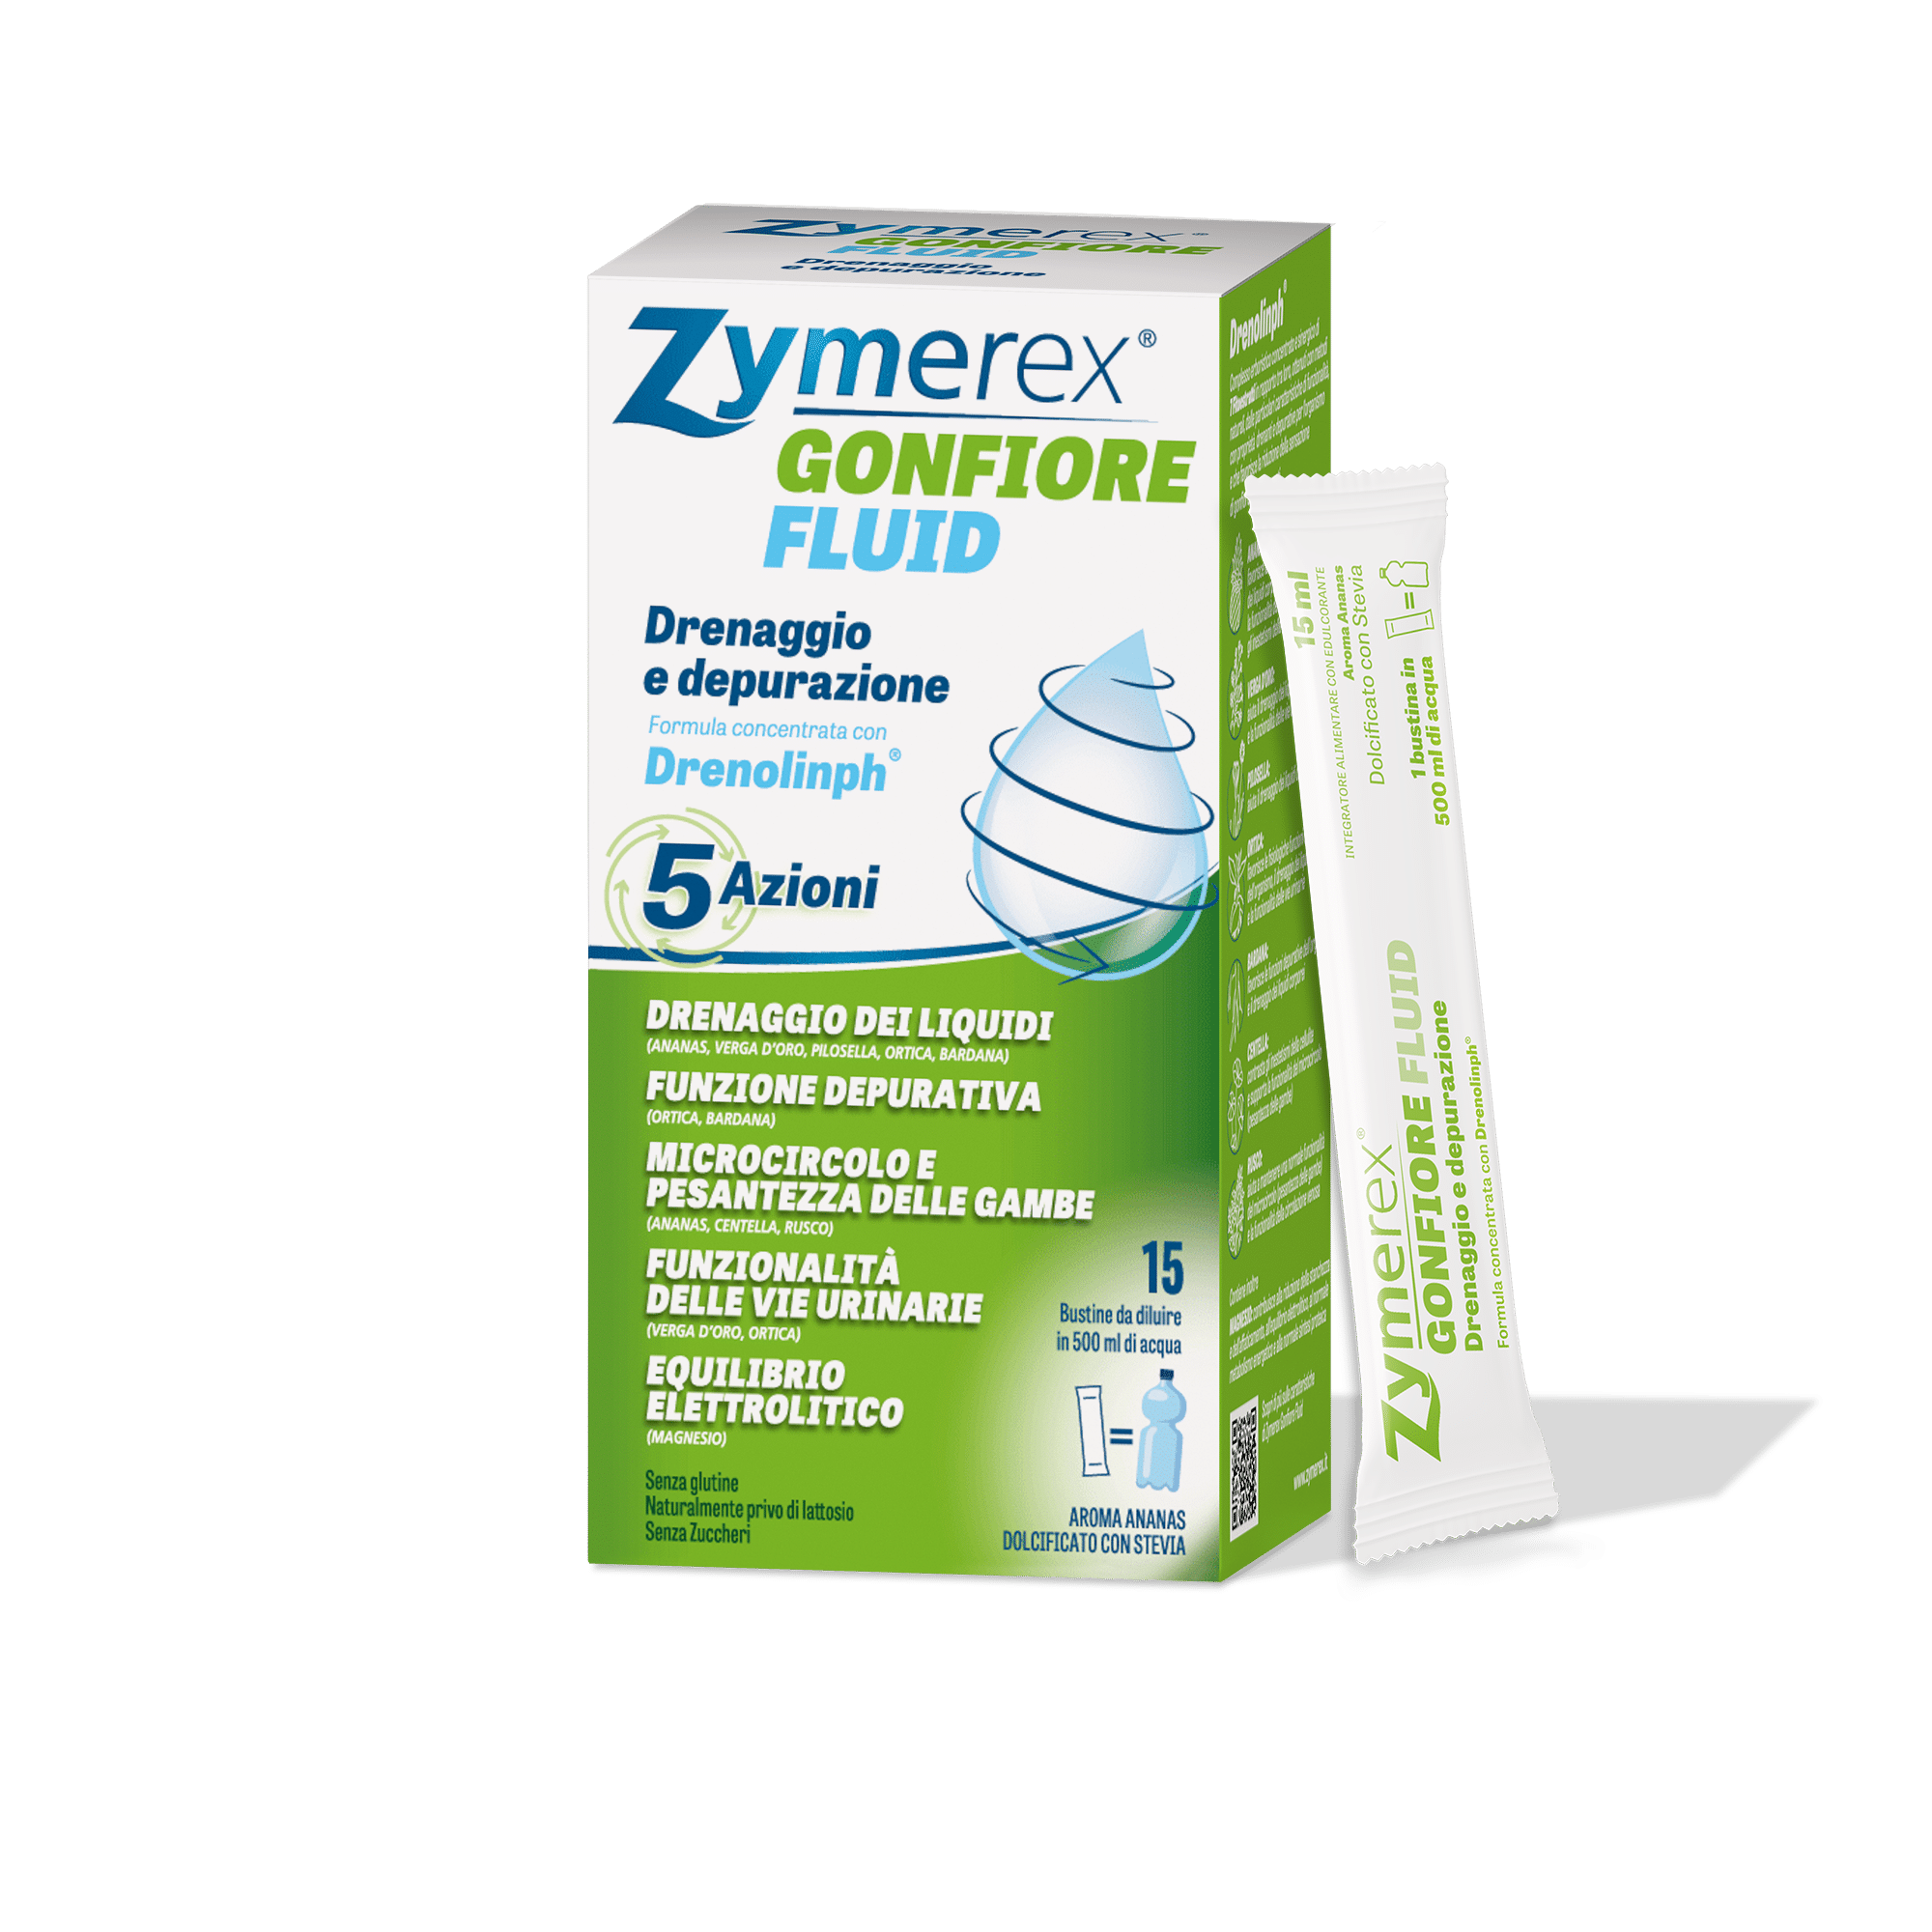

Zymerex GONFIORE FLUID

Prezzo suggerito: 14,90€

Disponibile in farmacia e parafarmacia

Zymerex Gonfiore Fluid è un integratore liquido in bustine, in formula concentrata con Drenolinph, un pool di 7 estratti naturali che stimolano l’azione drenante e detossinante dell’organismo, favoriscono la riduzione della sensazione di gonfiore e gambe pesanti, stimolano il drenaggio dei liquidi corporei e contribuiscono a una sensazione di leggerezza e benessere generale. Contiene inoltre Magnesio, per favorire l’equilibrio elettrolitico. Zymerex Gonfiore Fluid aiuta a bere più acqua. I glicosidi dello steviolo dolcificano naturalmente il prodotto senza incidere sui livelli glicemici.

Disponibile in due gusti: ananas e frutti rossi.

CINQUE AZIONI CONTRO I LIQUIDI IN ECCESSO

Formula concentrata con Drenolinph

Complesso erboristico concentrato e sinergico di 7 Fitoestratti (ananas, bardana, centella, ortica, pilosella, rusco, verga d’oro) in rapporto tra loro, ottenuti con metodi naturali, dalle particolari caratteristiche di funzionalità, con proprietà drenanti e depurative per l’organismo e che favorisce la riduzione della sensazione di gonfiore e gambe pesanti.

Zymerex Gonfiore Fluid – 15 bustine da sciogliere in acqua

Si consiglia di assumere 1 bustina al giorno diluita in 500 ml di acqua.

15 bustine da 15 ml da sciogliere in acqua.

Disponibile in 2 gusti: ananas e frutti rossi.